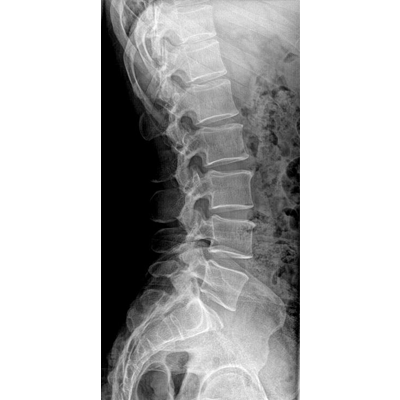

高品質影像鏈 讓您看的更清晰 PLX8500C/D

●大尺寸非晶硅平板探測器。

●探測器可以大范圍轉動,大尺寸有效探測面積,可滿足人體多部位攝影需求。